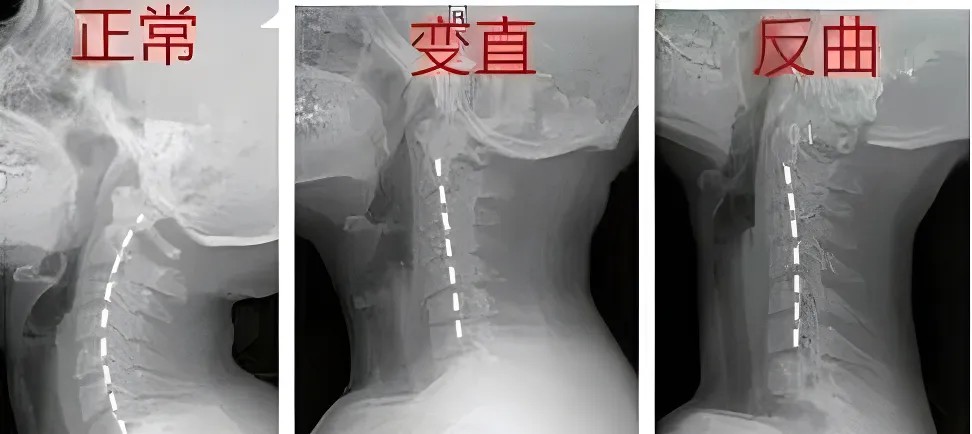

這些報(bào)告單上,常寫著“頸椎曲度(弧度)消失”、“頸椎變直”或者是“頸椎曲度反弓”,很多人看到后,一下子就慌了:這頸椎出問題可不是小事,曲度是什么呢?

嬰兒在學(xué)習(xí)爬行和抬頭的過程中,頸椎的生理曲度逐漸形成,在頸部呈現(xiàn)出一個(gè)開口向身體背側(cè)的“C”形;

脊柱的生理曲度就像彈簧一樣,它的存在能有效減輕外力的沖擊震蕩,保護(hù)脊髓和大腦,維持姿勢(shì)的穩(wěn)定。

頸椎曲度變化給我們帶來的最直接的感受便是反復(fù)出現(xiàn)的頸項(xiàng)部板滯發(fā)緊、僵硬酸痛,甚至頭目昏脹,伴或不伴有頸椎“咔咔”響聲。

需要指出的是,單純的“頸椎生理曲度變直”并不是頸椎病,但說明頸椎正處于不健康的狀態(tài),若再不注意,頸椎生理曲度消失,頸椎間盤張力增高,就會(huì)導(dǎo)致頸椎纖維環(huán)破裂、椎間盤膨出,誘發(fā)頸椎病。

此外,頸椎曲度變直或者反曲時(shí),頸部肌肉、筋膜等軟組織會(huì)發(fā)生改變,也會(huì)成為引發(fā)頸椎病的結(jié)構(gòu)與生理基礎(chǔ)。